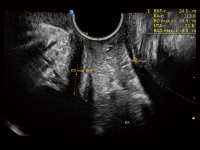

豐富的血流動(dòng)力學(xué)檢測(cè)技術(shù),可在不同醫(yī)療場(chǎng)景中高效捕捉血流信號(hào),助力臨床診療。

在傳統(tǒng)血流的基礎(chǔ)上優(yōu)化掃查和算法策略,能夠更好的抑制組織信息,提煉紅細(xì)胞運(yùn)動(dòng)信息,得到更高幀頻,高靈敏度和分辨率的血流信號(hào),還原更真實(shí)的血流動(dòng)力學(xué)。

通過(guò)創(chuàng)新的Matrix E自適應(yīng)濾波算法,能有效濾除軟組織和噪聲信號(hào),最大限度保留超低速微細(xì)血流的信號(hào);結(jié)合超長(zhǎng)時(shí)間域算法,極大提升細(xì)微血流的敏感性和空間分辨率,更真實(shí)的反應(yīng)組織、包塊的血流灌注情況。